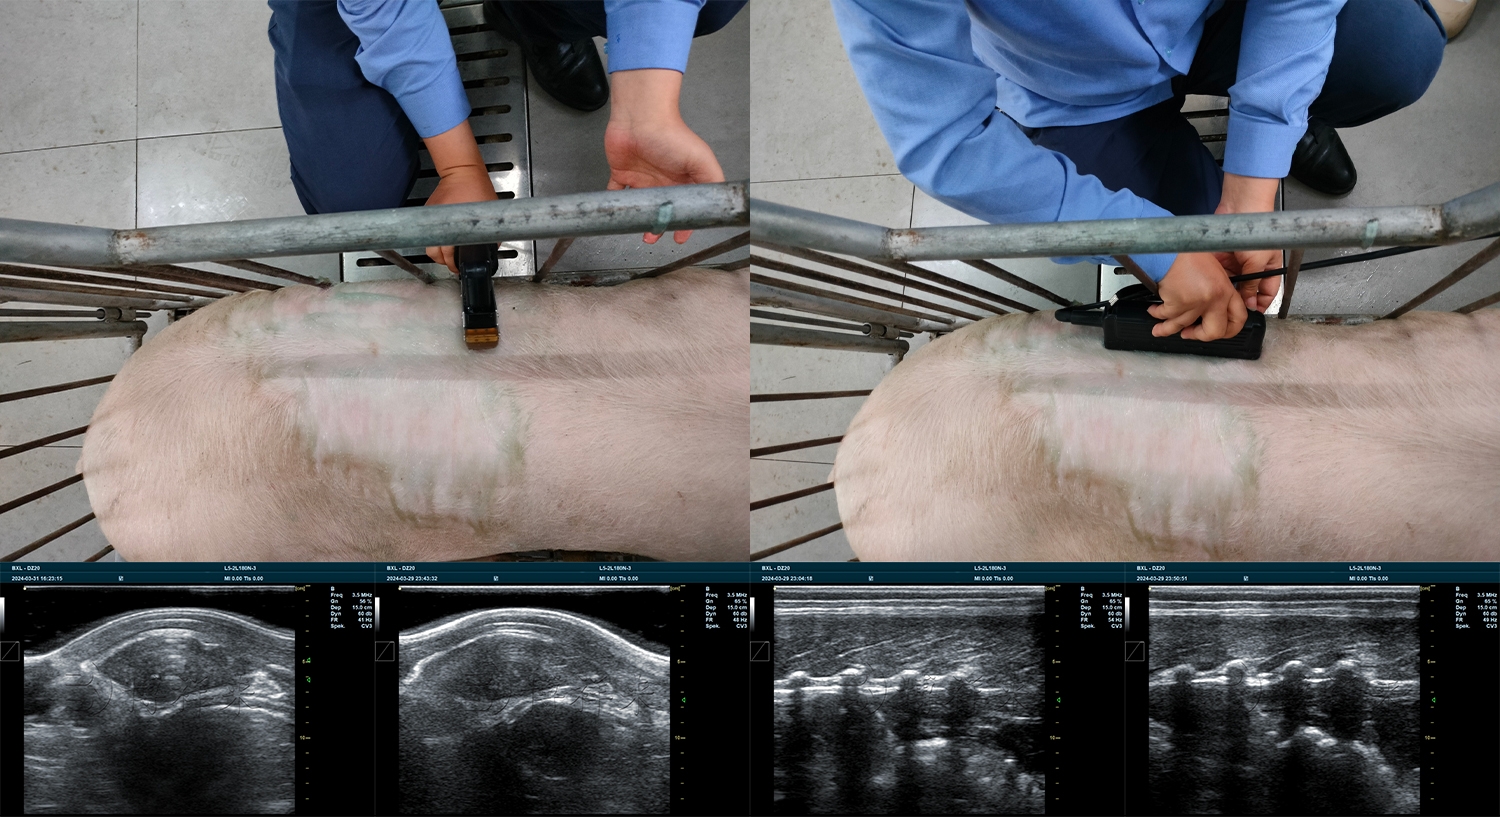

猪背膘眼肌的厚度和面积是评估种猪瘦肉率、生长速度和饲料转化率的两个最关键指标。在现代育种工作中,猪用背膘眼肌测定仪取代了传统依靠经验或屠宰测量的方法,实现了对活体猪只的精准、无损测量。

以下是使用猪用背膘眼肌测定仪(如博祥来BXL-DZ20等)进行标准检测的详细操作步骤和技术要点。

探头放置: 将探头垂直于猪背中线放置在第二测点 (P2) 上。P2是测量猪背膘眼肌的核心位置。

图像调节: 根据屏幕显示的图像,轻微调整探头压力和角度,确保图像清晰,可以清晰分辨皮肤、脂肪层和肌肉层的边界。

测量背膘厚度: 图像上应显示三层脂肪(外层、中层、内层)和眼肌。

测量从皮肤外缘到内层脂肪与肌肉层(眼肌)交界处的垂直距离。部分猪用背膘眼肌测定仪可自动进行多层背膘测量。

测量眼肌面积:

将探头旋转至与脊椎平行的方向(沿着猪背中线)。

确保屏幕上完整显示长方形的眼肌(最长背肌)横截面。

使用猪用背膘眼肌测定仪的内置计算功能,沿眼肌边界进行描迹(Trace)或使用内置的椭圆/矩形工具进行拟合,自动计算出眼肌的面积。